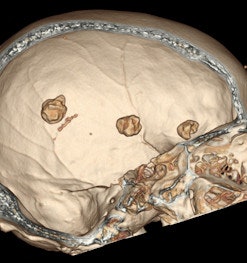

Because of its multiplanar reconstruction and 3D reconstruction capabilities, CT has supplanted the use of skull x-rays in the diagnosis of intracranial pathology. Also, CT is better than MRI in identifying and characterizing intracranial calcification, although newer MRI sequences are promising. In certain clinical situations, neurological symptoms correlate better with MRI findings than with the corresponding CT-identified calcifications.

Macroscopic calcifications are present in meningiomas in up to 60% of cases, the pattern of which may range from diffuse, rim, or sand-like to focal or even globular. Calcified meningiomas can be associated with focal thickening of the overlying skull bones or with dilatation of the adjacent air-containing sinus of the skull base, they stated.